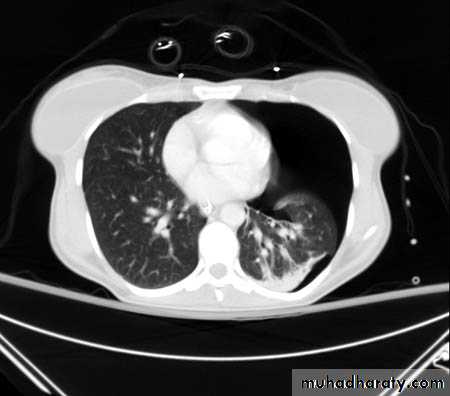

CT scan

BronchoscopyPneumothorax

Emphysema